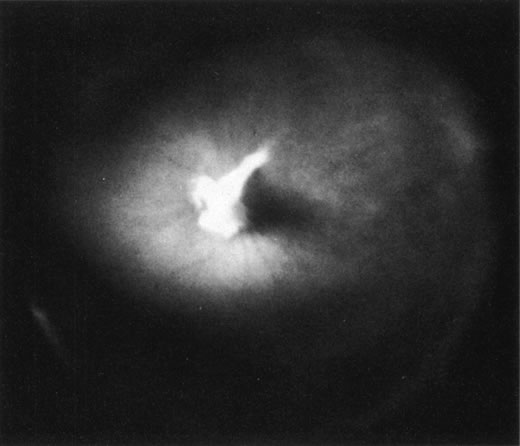

Fig. 10. A. Cystic retinal tuft. The tuft is a cystoid formation of fibers, similar to those of the nerve fiber layer, and cells similar to those found in the inner plexiform layer of the retina. The tuft is connected to the internal limiting lamina of the retina. This scanning electron micrograph shows the insertion of the vitreous collagen fibers on the tuft's apical surface. Their orientation changes toward the tuft's surface. B. Verruca. The verruca has a structure similar to that of a tree. Its “roots” are embedded in the inner layers of the retina. Cellular elements resembling cells of the inner plexiform layer can be seen near the retinal surface. The “trunk” of this structure extends from the retina to the middle parts of the vitreous cortex. The “branches” of the verruca are intertwined with interrupted vitreous collagen fibers. Local condensation of collagen fibers exists as well as local collagen destruction (arrows) and interruption of the internal limiting lamina of the retina. (Photographs courtesy of Dr. Stephan Dunker.153)